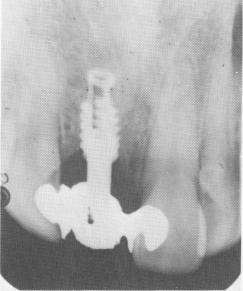

Fig. 8-29. A postoperative periapical radiograph.

2 Postoperative xray of single tooth upper endosseous implant shaft